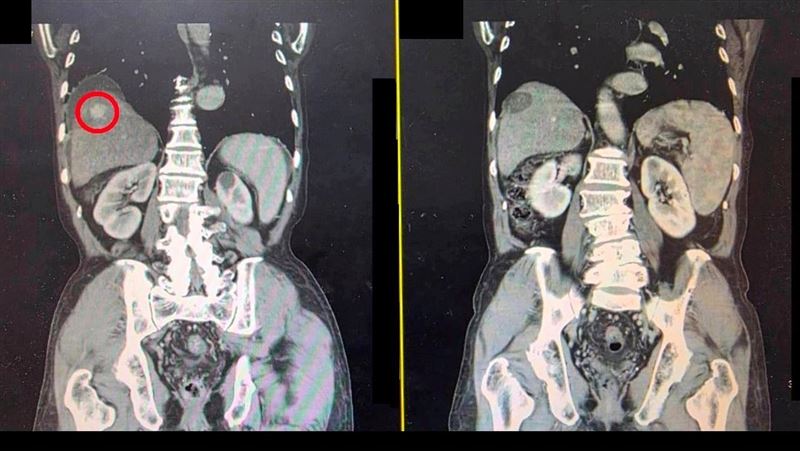

▲病人檢查發現有一將近3公分的肝腫瘤(紅圈處),接受治療後,腫瘤已消除。(圖/大千綜合醫院提供)

大千綜合醫院肝膽腸胃科醫師林德福表示,這名70歲的陳先生肝硬化非常嚴重,一開始無法治療肝腫瘤,因此先以B型肝炎的抗病毒用藥及利尿劑等藥物控制肝硬化的情形,等到肝功能改善後,再使用超音波導引微波消融術,精準消滅腫瘤。由於肝腫瘤長在肝臟的右葉且接近橫隔膜下方,因此治療過程中注入人工腹水,將肝臟與橫隔膜分開,避免橫隔膜損傷。完成治療後隔天,病人沒有明顯併發症,即出院返家;三個月後接受電腦斷層追蹤檢查,已沒有存活的肝腫瘤,順利恢復健康。